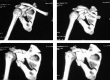

Objectives: This study aimed to evaluate the clinical outcomes of 20 surgically treated patients with displaced glenoid fractures after stabilization with distal radius plate.

Methods: Between 2012 and 2015, at 2 centers (HMCH & SHCE) of Bhubaneswar Odisha, we stabilized 20 scapular intra-articular fractures surgically with distal radius locking plate and studied the outcome of the surgeries. The outcome of the 20 fractures was determined using the Constant and Murley score. Both shoulders were assessed and the score on the injured side was given as a percentage of that on the uninjured side.

Conclusions: Various fixation modalities have been described in the literature, however fixation of intra-articular fracture of glenoid with distal radius locking plate for articular reconstruction in the presented series provides good functional outcome with early restoration of the range of motion of the shoulder.